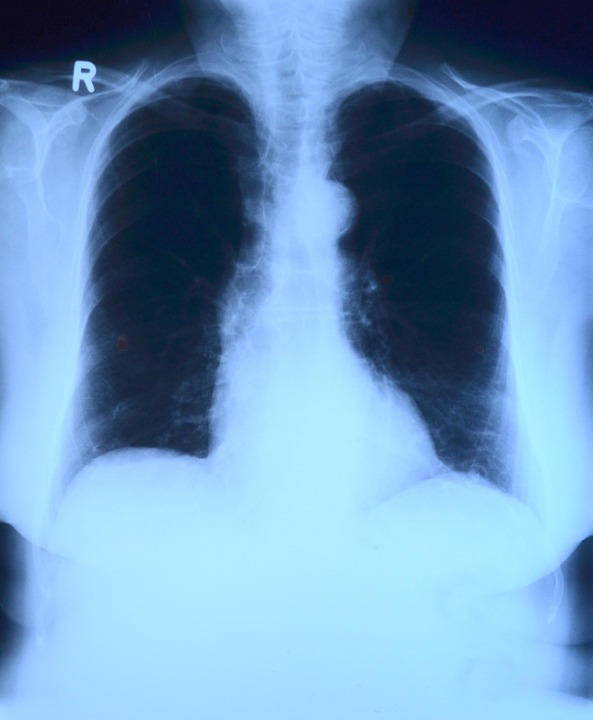

1. Conventional X-rays

These are the most common type, producing 2D images of the internal structures of the body. They are widely used for diagnosing bone fractures, infections, and certain cancers.